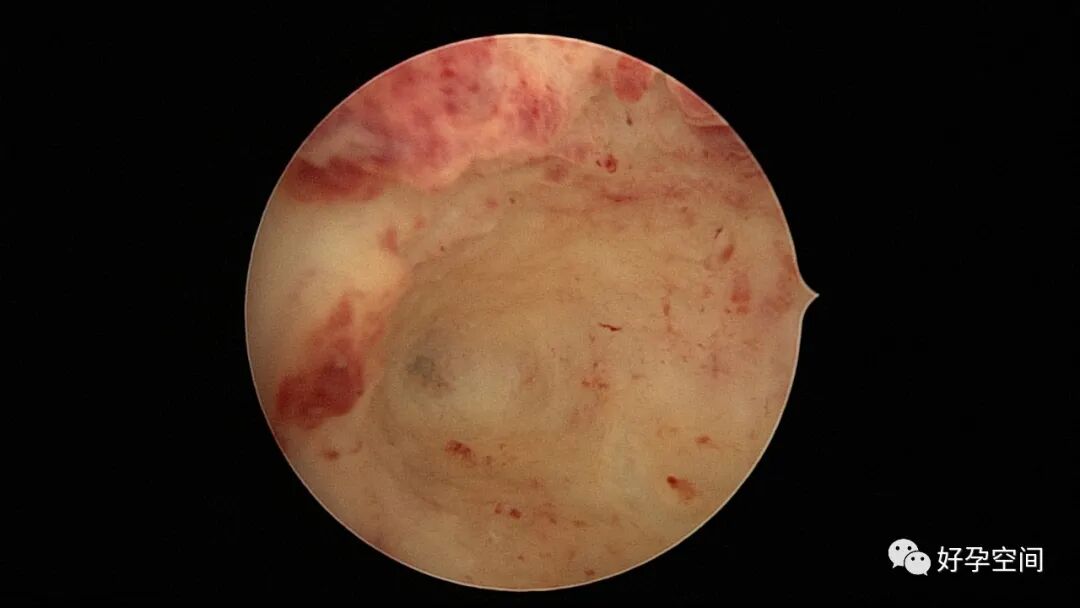

病例2:患者31岁,原发不孕,2019年11月在重庆某妇幼保健院做宫腹腔镜手术疏通输卵管,术中未取内膜活检,术后未孕。2021年7月在成都某大型生殖中心试管怀孕双胎(移植前未做宫腔镜检查及内膜活检),2021年11月孕4月双胎破水,在达州当地医院引产清宫,清宫术后40天复诊B超提示宫腔胚物残留。2022年1月到我院(眉山蕴缨妇产医院)行宫腔镜手术切除残留组织,2022年4月宫腔镜术后3个月复诊B超提示宫腔粘连,再次来我院行宫腔镜分粘。宫腔被覆一层沙丘状质脆增生组织,宫腔下段两侧壁内聚,行分粘术,取内膜送病检。

子宫内膜结核是由结核分枝杆菌在子宫内膜部位种植引起的炎症,是仅次于输卵管结核的常见女性生殖器结核。子宫内膜结核常由输卵管结核蔓延而来,多继发于盆腔腹膜结核或肺结核。子宫内膜结核的超声表现主要为:子宫内膜回声不均匀、宫腔内结节样病灶、宫腔内强回声灶、单纯的子宫内膜薄等。盆腹腔超声显示输卵管炎性表现:输卵管增粗、肥厚、扭曲、僵硬、输卵管积液积脓、卵巢旁混合性包块、输卵管系膜囊肿、盆腔包裹性积液等。术中所见:盆腹腔组织粘连、盆腹腔粟粒样结节、结核球、脓肿等,输卵管伞端烟斗样外翻,输卵管内充满淡黄色干酪样或豆渣样组织。宫腔镜显示宫腔狭窄、宫壁僵硬、宫内膜肉芽肿样增生、内膜质脆易刮除、干酪样组织、脓液等。

温宝宁等将子宫内膜结核宫腔镜检查的镜下表现分为:①宫腔形态、大小正常,双侧输卵管开口可见,子宫内膜发红、增厚,局部突起,表面可见少量质脆的小颗粒状赘生物,可刮出质脆的子宫内膜组织;②宫腔形态正常,但是宫腔内无正常子宫内膜,均被覆一层苍白的绒毛状或棉絮状质脆组织,血管少,无异形血管,宫腔内病灶与正常组织分界明显;③宫腔形态异常,呈窄桶状,子宫内膜瘢痕化,输卵管开口细小,甚至宫角消失。